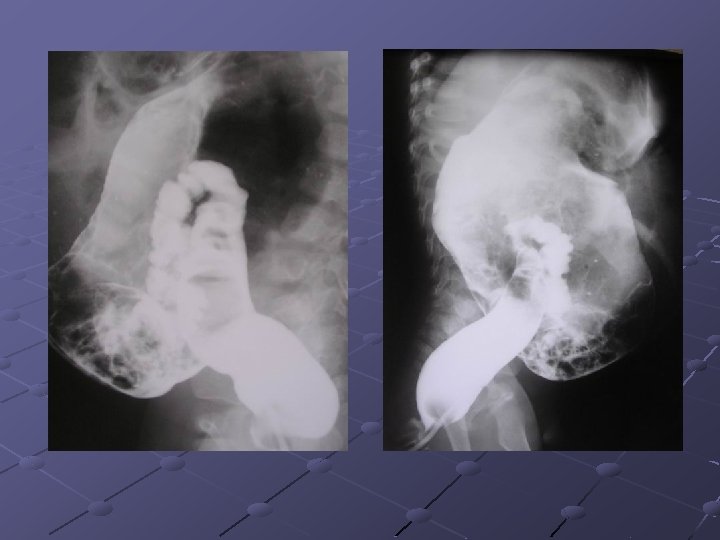

Cas n° 5 17 mois Histoire médicale antérieure = o Pleurs, douleurs abdominales

3, 7 x 2, 8 cm Depuis le rectum hypochondre gauche

INVAGINATION INTESTINALE AIGUE (IIA) Télescopage et penetration d’ un segment intestinal dans le segment d’ aval. Urgence diagnostique et thérapeutique: compression vasculaire ischémie et nécrose Nourrisson ( 80 % entre 6 mois et 2 ans ). Maximum entre 4 et 12 mois (I). Avant 3 mois ou après 5 ans (II). Prédominance masculine ( 3 G/2 F).

Idiopathique ( 90% des cas ): adénolymphite mésentérique(caractère saisonnier ) Secondaire: lymphome digestif, meckel, duplication digestive , polype , purpura rhumatoïde , troubles fonctionnels post chirurgicaux , impactions digestives ( mucoviscidose. . ) Formes anatomiques: iléo-iléale n iléo-colique n Appendico-colique n colo-colique n diam. boudin < 20 mm diam. boudin > 25 mm Diagnostic = échographie et non l’ASP Traitement: - Lavements (air, hydrosoluble, eau) - Chirurgie Contre-indications des lavements: péritonite, choc